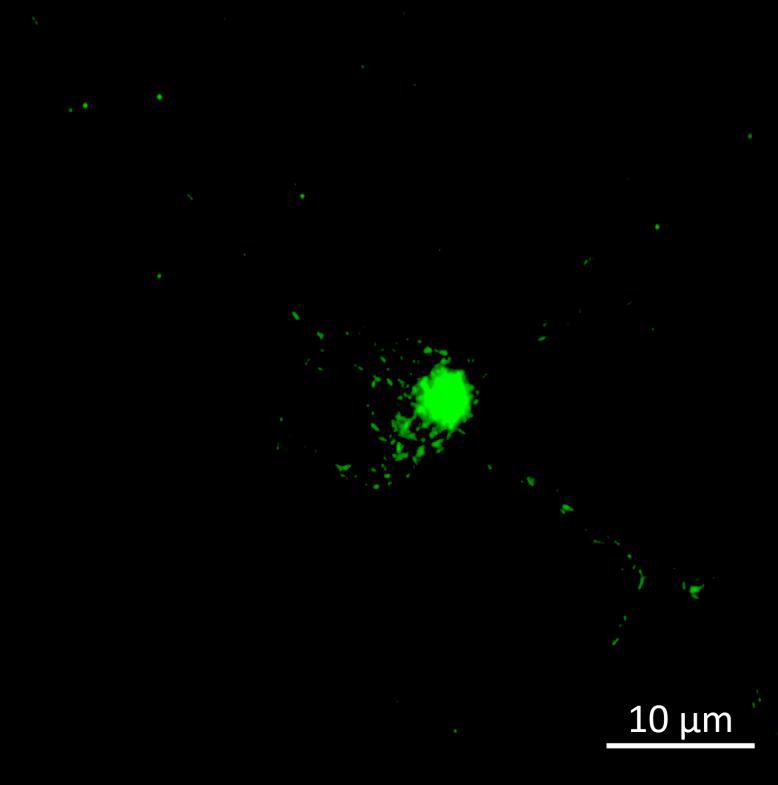

• Wildtype neurons were transduced with a lentivirus to express a full-length 4R tau isoform with a familial frontotemporal dementia P301L mutation labelled with EGFP

• Neurons were then exposed to recombinant tau preformed fibrils (PFFs) and imaged

• Increasing over time, PFF exposure induced areas of bright EGFP-positive aggregates of full-length tau, and aggregation of the K18 fragment FRET pair as seen by positive normalised FRET (NFRET) signal

0N4R-EGFP tau 2 weeks post-PFF

K18 FRET biosensor system 2 weeks post-PFF